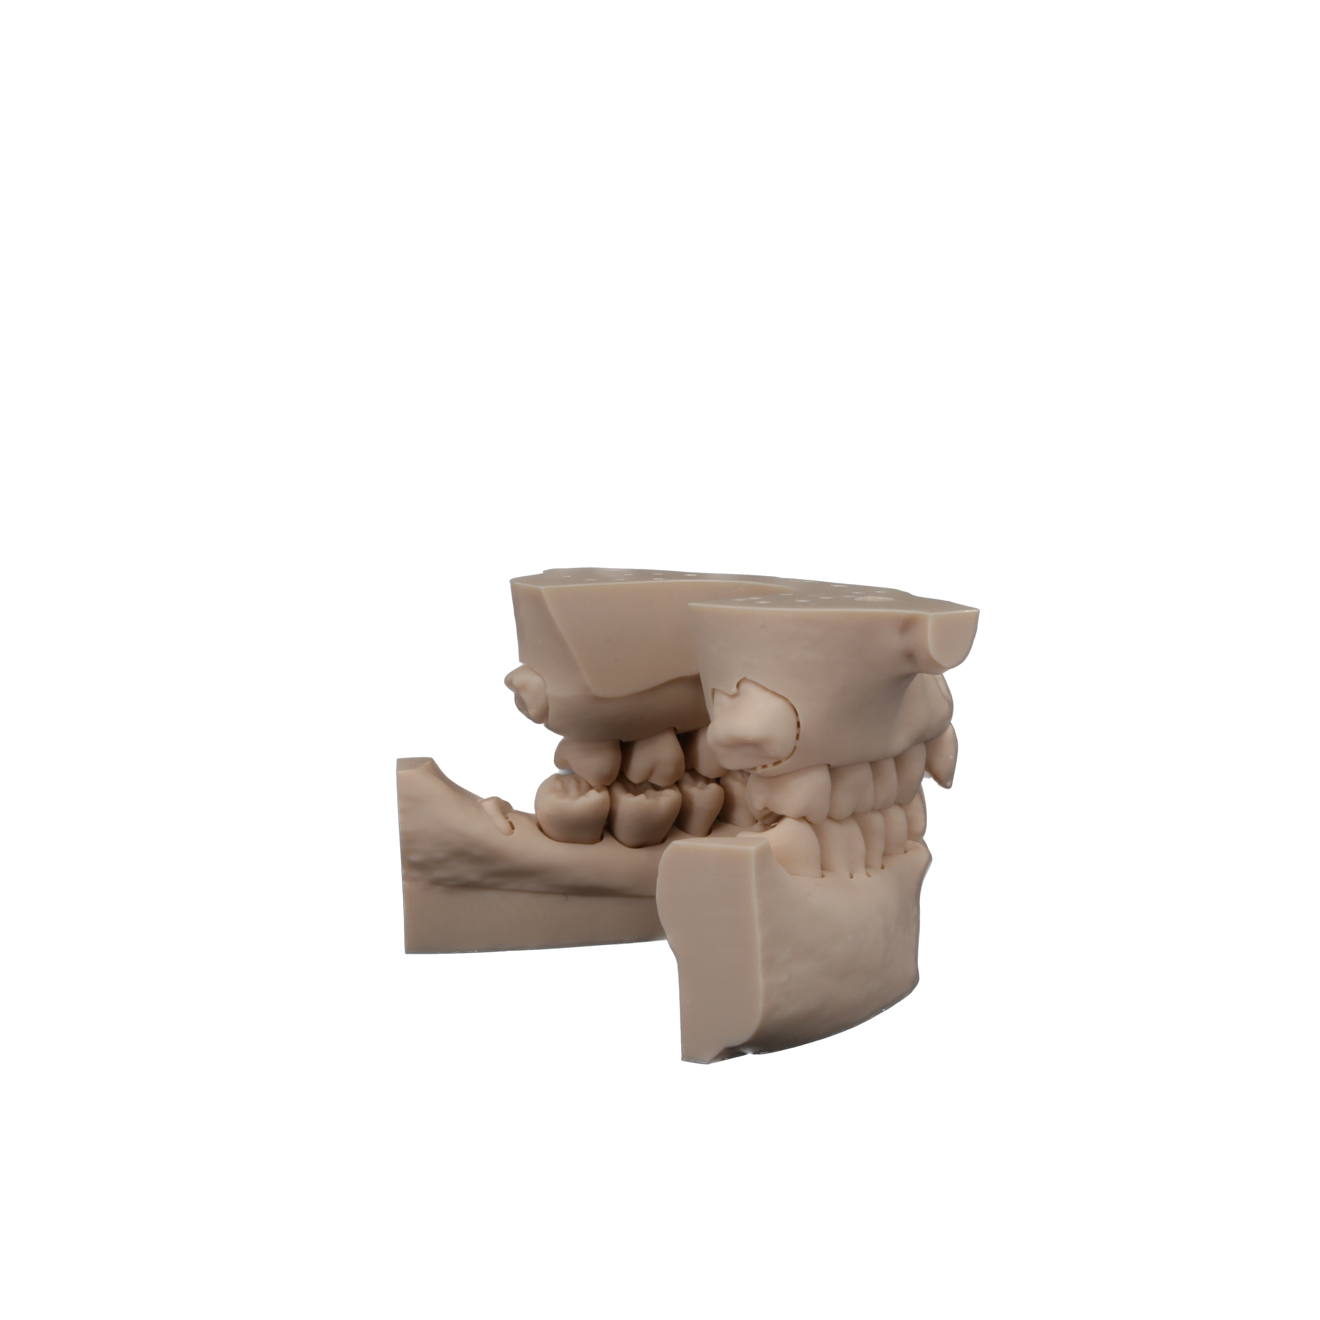

Fig. 1: The increasing adoption of 3D printing in the field of dentistry helps advance design and manufacturing of dental models. (All images: Rakesh Jivan)

As their name suggests, typodont models feature maxillary and mandibular arches of perfect teeth with an idealised occlusion typically manufactured from acrylic or thermosetting plastics which are more difficult to cut than natural teeth. They generally lack the fine intricacies and complexity of natural human anatomy, limiting their potential to accurately simulate real-life presentations in dental practice (Fig. 1).

The starting point for Oratomic4D was selecting a real patient to replicate. After an extensive search, the patient, Tina, was chosen for her ideal oral anatomy and range of treatments that could be simulated. Unlike a typodont model, Tina had mild crowding, impacted maxillary and mandibular third molars, and complex root canal anatomy (Figs. 2–7).

These irregularities in Tina’s oral anatomy made her an ideal candidate for the creation of a range of realistic simulation models that are highly representative of the types of patients encountered in dental practice.